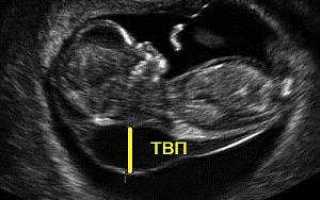

Итак, что такое воротниковое пространство у плода? Это ультразвуковой маркер, указывающий на возможные хромосомные аномалии. Толщина воротникового пространства (ТВП) — это ширина области в шейном отделе позвоночника, заполненная подкожной жидкостью. Термин «воротниковое пространство» введен в 1996 году и используется в скрининговых исследованиях во многих развитых странах.

Исследование воротниковой зоны плода проводится с 11 по 13 недели беременности, во время первого УЗИ. В этот период результаты наиболее информативны. Ранее 11 недель исследование нецелесообразно, так как плод слишком мал. После 14 недели лимфатическая система начинает поглощать жидкость, и этот показатель теряет диагностическую ценность.

Толщина шейно-воротниковой зоны у плода измеряется с помощью трансабдоминального или трансвагинального ультразвукового исследования. Чаще используется трансабдоминальное УЗИ; трансвагинальный метод применяется, если первый не дает полной информации. Некоторые специалисты комбинируют оба подхода для более точной оценки.